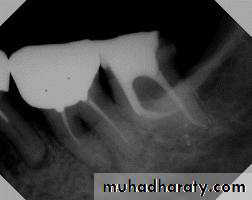

• Proper reading of the preoperative (diagnostic) radiograph to get information about the size and extent of the pulp chamber and internal changes (calcification or resorption).

• Radiograph from different angles (shifting technique).

Bur held alongside radiograph to estimate the depth

of penetration